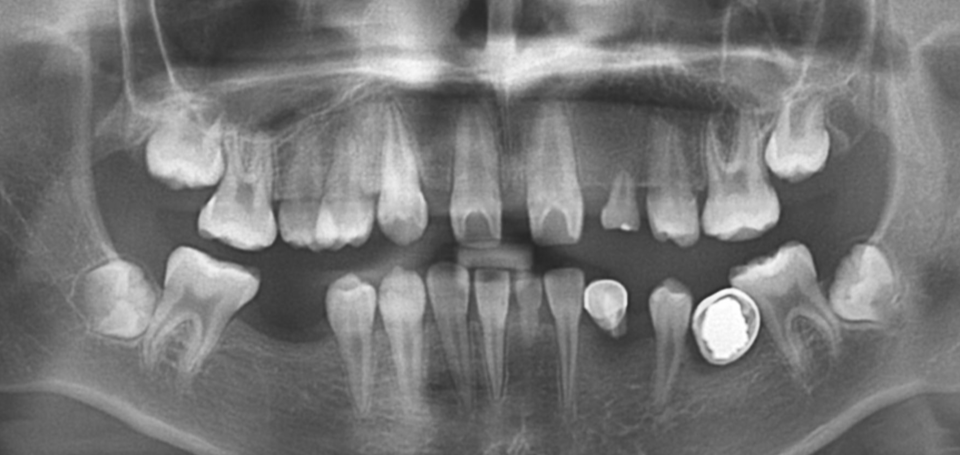

20세 남환으로 2013년 다수 영구치의 선천적 결손으로 내원하 여, 성장을 관찰하면서 교정치료를 진행하였다 [그림 10].

교정치료가 거의 완료될 시점에서 영구치 결손 부위인 #22, 23, 33, 34부위에 4개의 임플란트를 식립하기로 계획하였다 [그림 11].